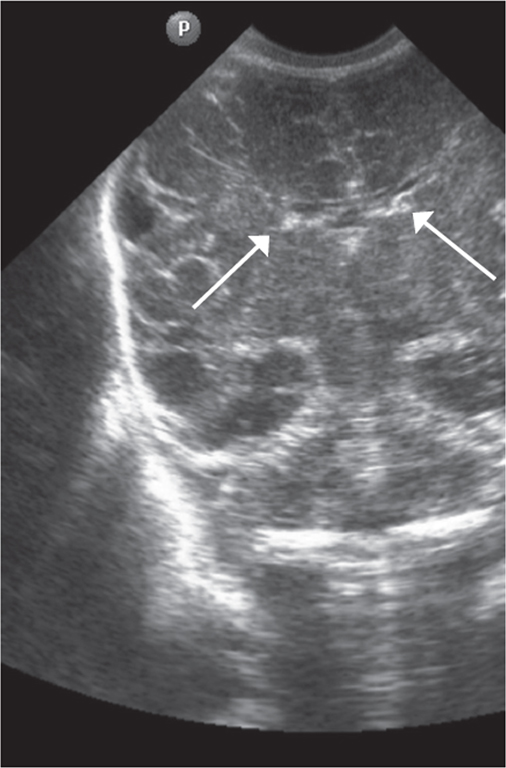

The first CUS was performed by using the anterior fontanel for all neonates (4 premature neonates in gestational week 25, 5 premature neonates in gestational week 26, and three premature neonates in gestational weeks 27, 28, and 29). Every preterm neonate underwent once daily ultrasound B brain scanning using the standard method with microconvex and linear transducers (5–7 Hz) [14]. Thickness of the visualized germinal matrix was measured in millimeters (mm) in the anterior horn of the lateral ventricles using the CUS (the Monro foramen projection, Fig. 1).

Fig. 1. CUS image of preterm newborn, gestational age 28 wks., frontal scan. Arrows indicate the area of visualization of the germinal matrix

Рис. 1. Краниальная сонография недоношенного новорожденного, 28 недель гестации, фронтальный скан. Стрелками указаны области визуализации герминального матрикса